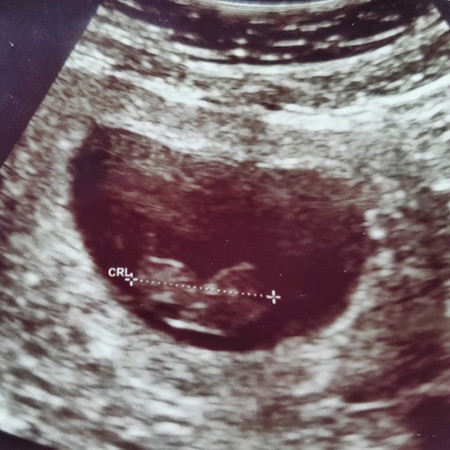

#บันทึกความจำอันแสนเจ็บปวด 06/02/2563 วันนี้หมอตรวจพบว่าหนูไม่มีหัวใจ แม่เกิดภาวะแท้ง หมอให้แม่ยุติการตั้งครรภ์นอนโรงพยาบาลวันนี้ แต่อาจารย์หมอท่านหนึ่งบอกว่า ผลอัลตร้าซาวด์ตั้งแต่แรกตอนเป็นก้อนเนื้อหนูมีหัวใจและสามารถโตได้ถึงวันนี้ เดือนที่แล้วหนูมีการเต้นของหัวใจ อาจารย์หมอขอให้รอปาฎิหารย์อีกสักครั้ง 11กุมภาพันธ์นี้ ถ้าหนูไหวหนูสู้กับแม่นะ ถ้าไม่ไหวไม่เป็นไร ครั้งหน้ามาเป็นลูกแม่อีกนะ แม่สัญญาจะดูแลหนูให้ดีกว่านี้ รักหนูมาก #น้องพอเพียง ????